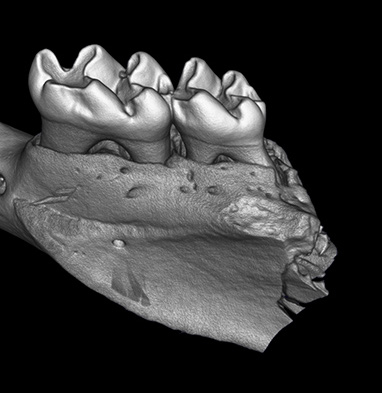

CosmoScan GX IIIは特に高い空間分解能を持ち、5µmまでの解像度と2.9µmのピクセルサイズ(FOV:8mm)を誇ります。これにより小さい骨の細かな解剖学的構造を含むex vivoサンプルの高品質な画像が得られます。

- 空間分解能 = 5µm 最小ピクセルサイズ = 2.9µm